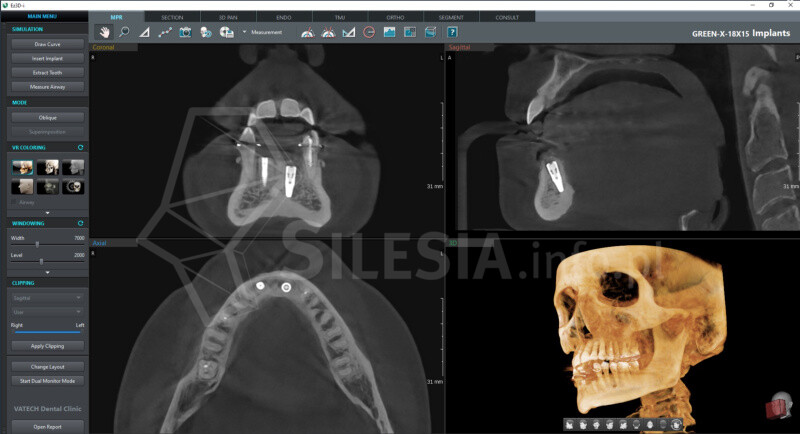

Pracownia wyposażona jest w tomograf stożkowy Vatech Green X (model 2025) – najnowszej generacji urządzenie, które łączy najwyższą jakość obrazów 2D i 3D z minimalną dawką promieniowania.

Skanowanie trwa zaledwie 2,9 sekundy, a technologia AI automatycznie redukuje zakłócenia i poprawia ostrość zdjęć.

Specjalny tryb Endo pozwala uzyskać obraz kanałów zębowych w najwyższej rozdzielczości – idealny w diagnostyce endodontycznej.

CBCT (tomografia stożkowa) to nowoczesne badanie 3D, które pokazuje zęby, kości, zatoki i stawy skroniowo-żuchwowe w pełnym trójwymiarze. Umożliwia bardzo dokładne zaplanowanie leczenia chirurgicznego, ortodontycznego, implantologicznego i laryngologicznego.